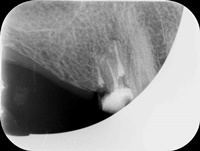

Reendo dolnej szóstki.

Wykonany zabieg resekcji wierzcchołka nie pomógł w ustąpieniu obajawów zapalnych. Skuteczne okazało sie dopiero reendo.